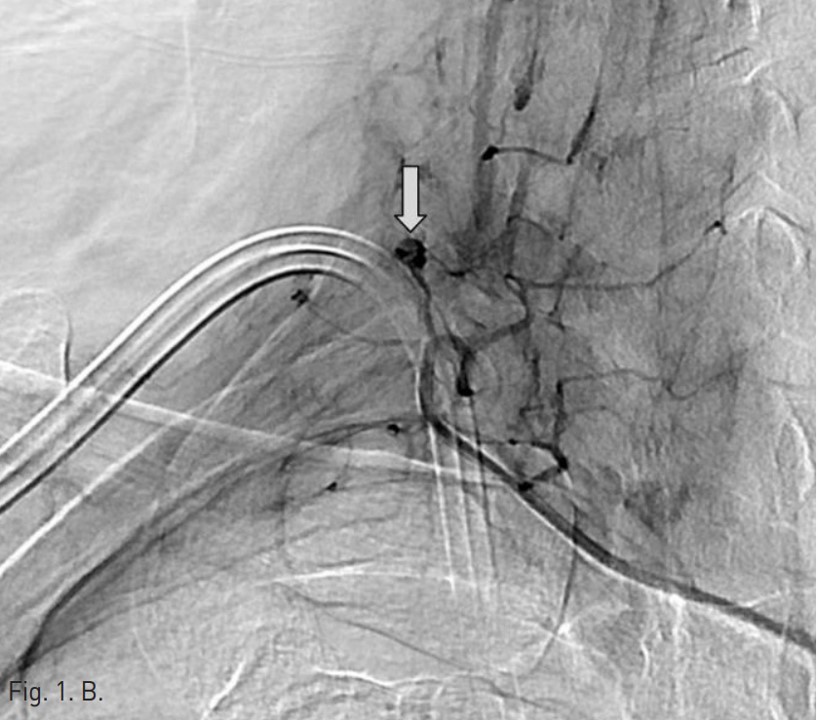

Permanent catheter insertion 이후 일주일 뒤 시행한 혈관조영술에서 갑상목동맥(right thyrocervical trunk)의 branch에 작은 거짓동맥류(small pseudoaneurysm)가 있고 permanent catheter를 insertion하는 과정에서 비롯된 합병증으로 판단되었음(Fig. 1A,B). 따라서 갑상목동맥의 기시부에서부터 아래 갑상동맥(inferior thyroidal artery)의 기시부까지 색전술을 시행하기로 함. Microcoil 및 glue를 사용하여 embolization 시행 후 조영제 검사에서 거짓동맥류는 보이지 않고(Fig. 2A,B) 임상 소견도 모두 호전되었음.

오른쪽 서혜부를 국소 마취 후 오른쪽 대퇴동맥을 천자하여 대동맥으로 카테터삽입술을 시행함. 그 후 guidewire를 통해 오른쪽 쇄골하 동맥 (right subclavian artery) 으로 진입하였고 조영술을 시행하여 갑상목동맥의 한 분지에 작은 거짓동맥류가 있는 것을 확인하였음(Fig. 1A,B). 이어서 2.2-F microcatheter with microwire(Progreat catheter, 150cm and Gold tip wire, Terumo)를 이용하여 거짓동맥류가 있는 분지로 진입하려 하였으나 혈관의 tortuosity가 심하여 시행하지 못함. 그래서 아래 갑상동맥의 기시부에서부터 갑상목동맥의 기시부까지 색전술을 시행하기로 하였고, microwire(Fathom, 0.016 inch, 160 cm, Cook)를 이용하여 아래갑상동맥으로 진입함.

Fig. 1. Selective angiography of the right thyrocervical trunk shows a pseudoaneurysm(arrow) from a branch of the right thyrocervical trunk.